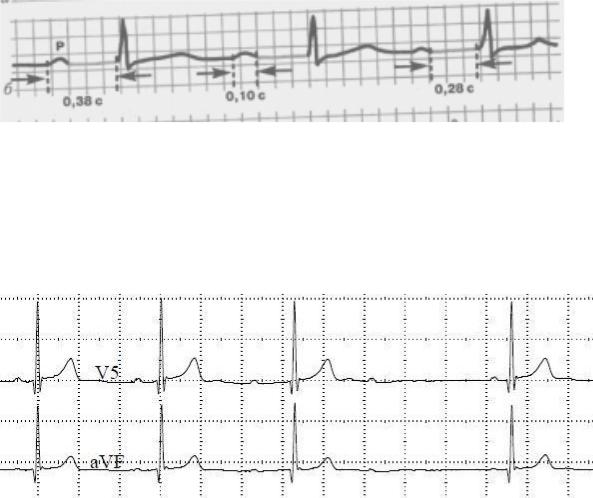

Рис. 8. Синдром WPW.

Для синдрома Вольф-Паркинсон-Уайта (WPW) характерно:

-укорочение интервала P-Q (<120мс)

-∆-волна на восходящем колене зубца R

-расширение комплекса QRS свыше 100мс

Тип А высокий R с ∆-волной присутствует в правых грудных отведениях II, III и aVF.

При В типе зубец R с ∆-волной регистрируется в левых грудных отведениях,

а также I и aVL. В то же время в отведениях II, III и aVF регистрируется желудочковый комплекс типа qR или QS, что может привести к ошибочной диагностике перенесенного инфаркта миокарда задней стенки.